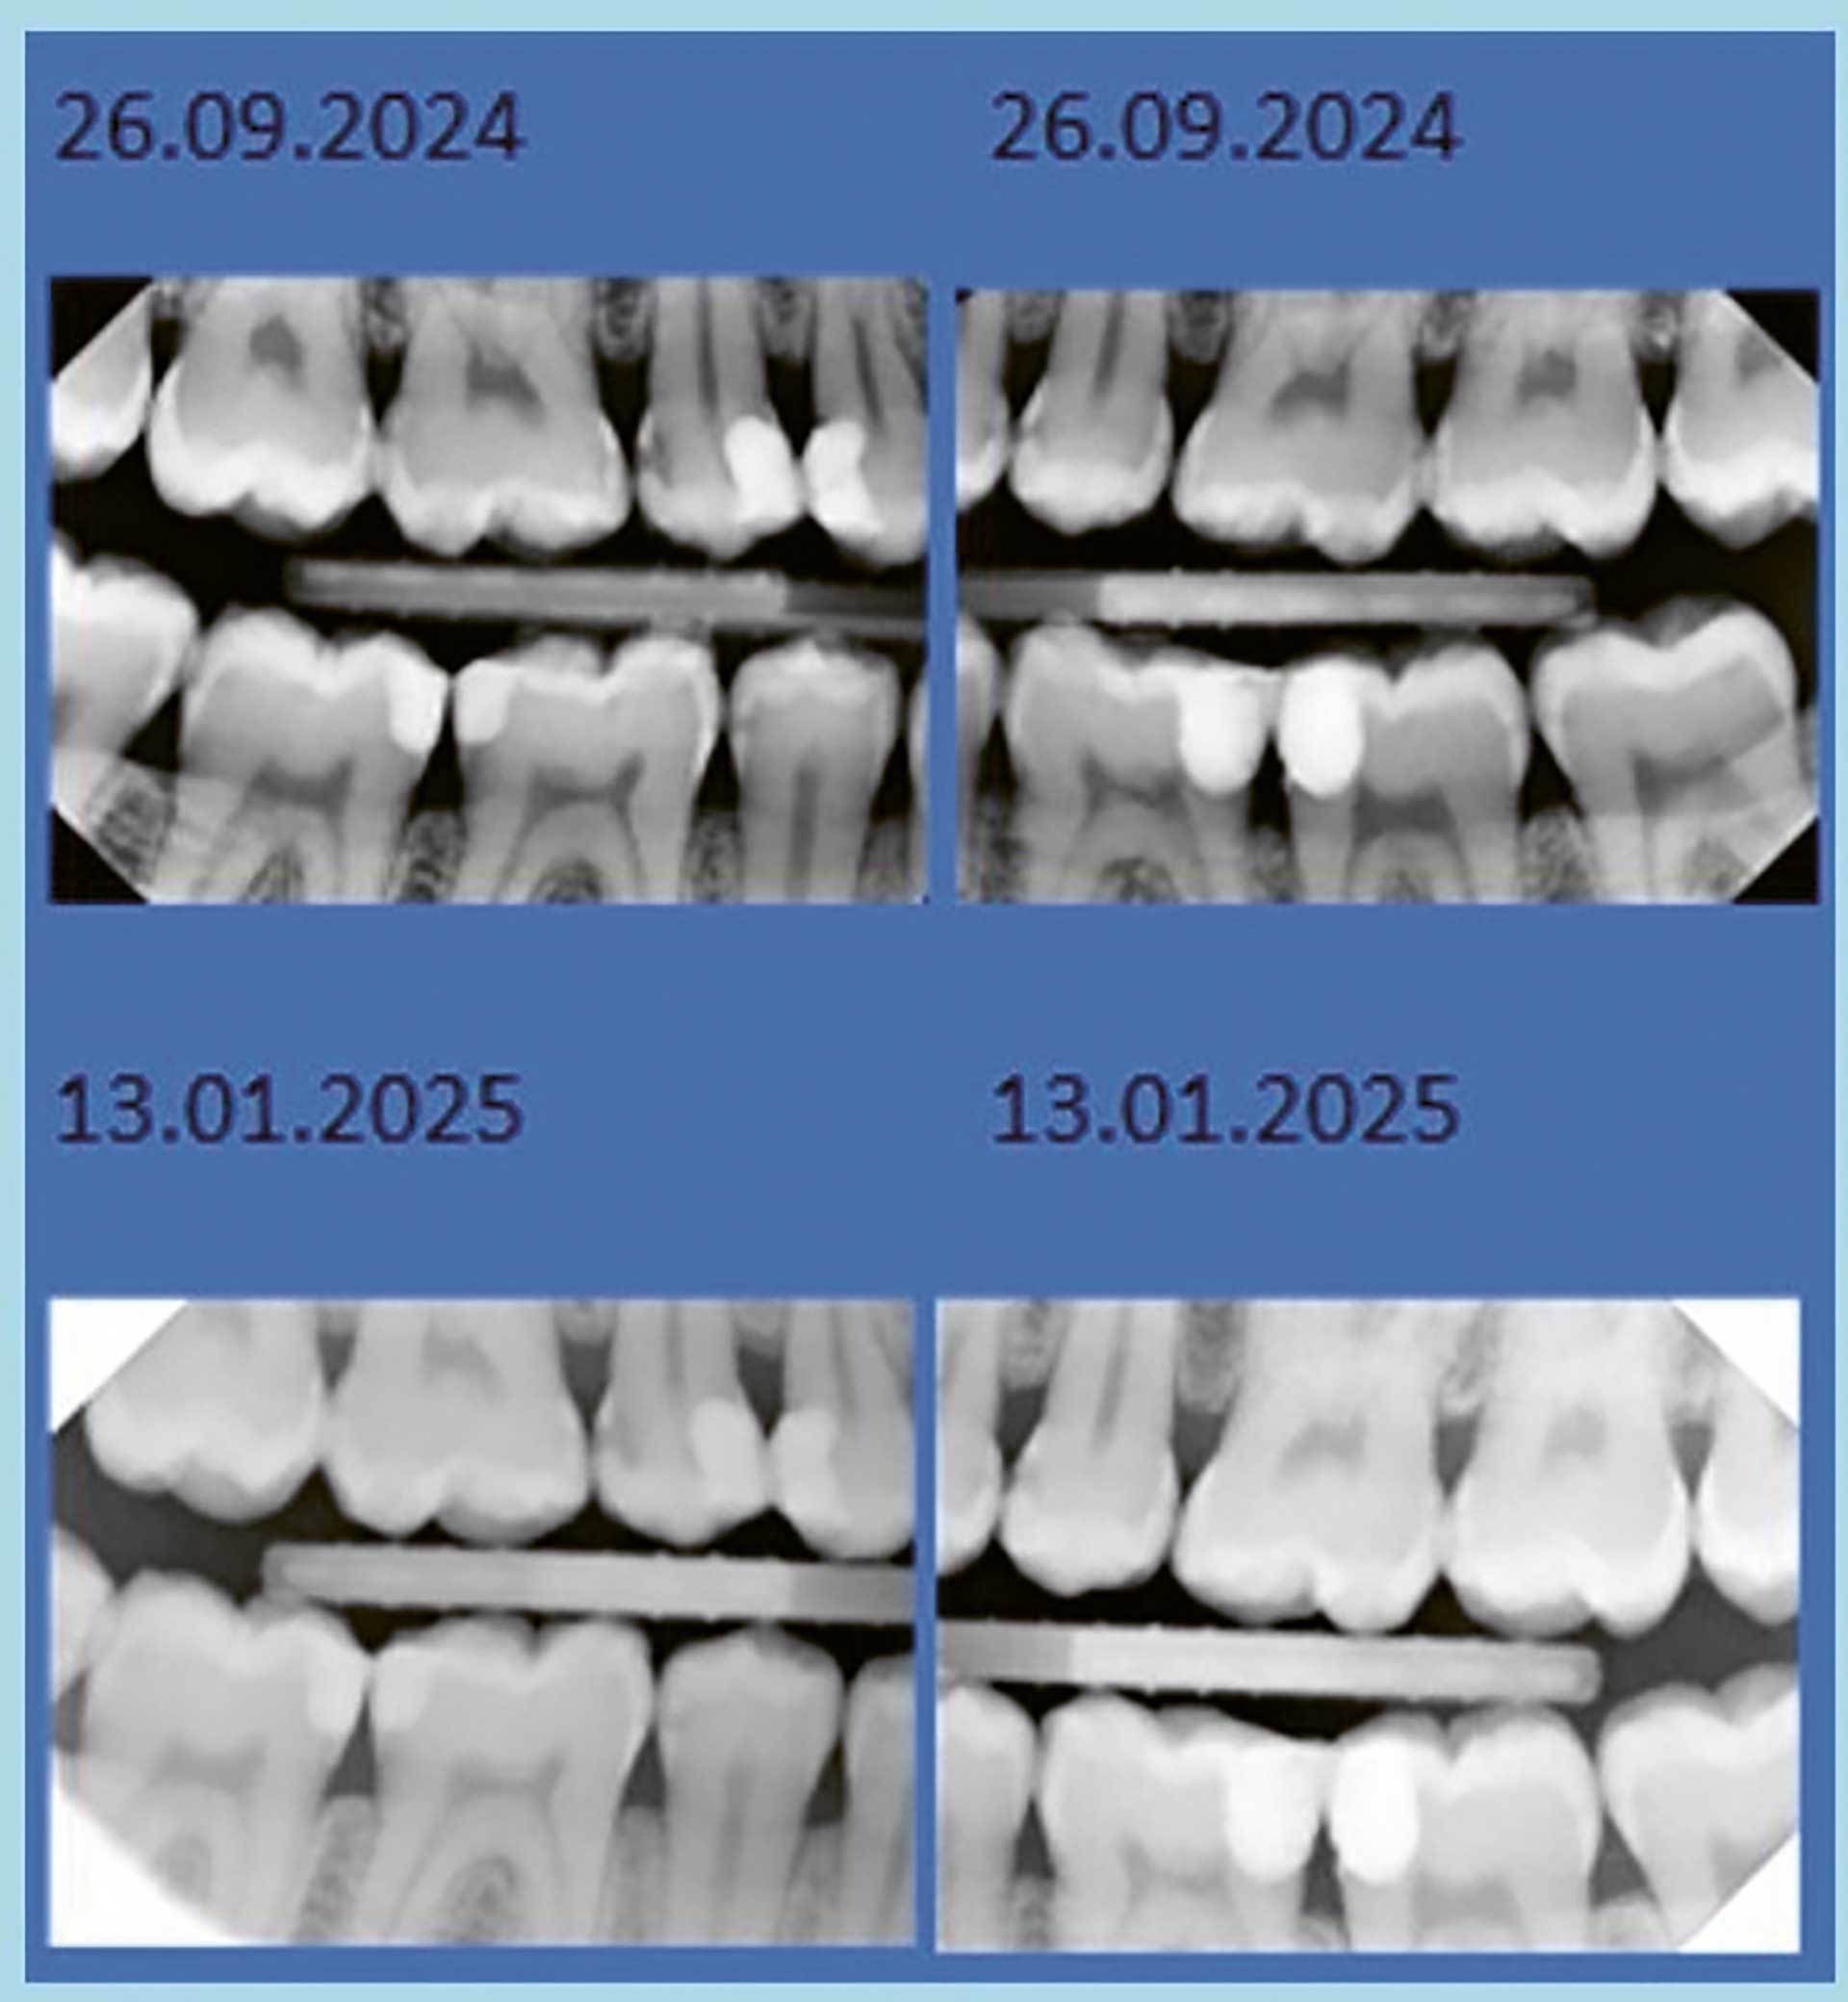

Figur 3. Viser stabile forhold og ingen progresjon i kariesutviklingen. Ved siste kontroll 13.01.2025 ble det tatt nye røntgenbilder. Vi kan se at lesjonene ikke har forandret seg siden forrige undersøkelse. Vi var spesielt oppmerksomme på tann 15 distalt, som ser ut til å ha stått uforandret.

Det er også viktig å påpeke at munnhelsepersonell må behandle videre karies til denne pasienten med årsaksrettet behandling, framfor kun operativt. Selv om pasienten virker motivert, er det viktig med videre motivasjon og nye vurderinger av kariessituasjonen. Det er viktig å innkalle pasienten til jevnlige kontroller for å opprettholde motivasjon og sikre at forebyggende tiltak – som fluoridpensling – gjennomføres systematisk. Som vist i figur 3, har forholdene vært stabile, uten tegn til progresjon i kariesutviklingen.